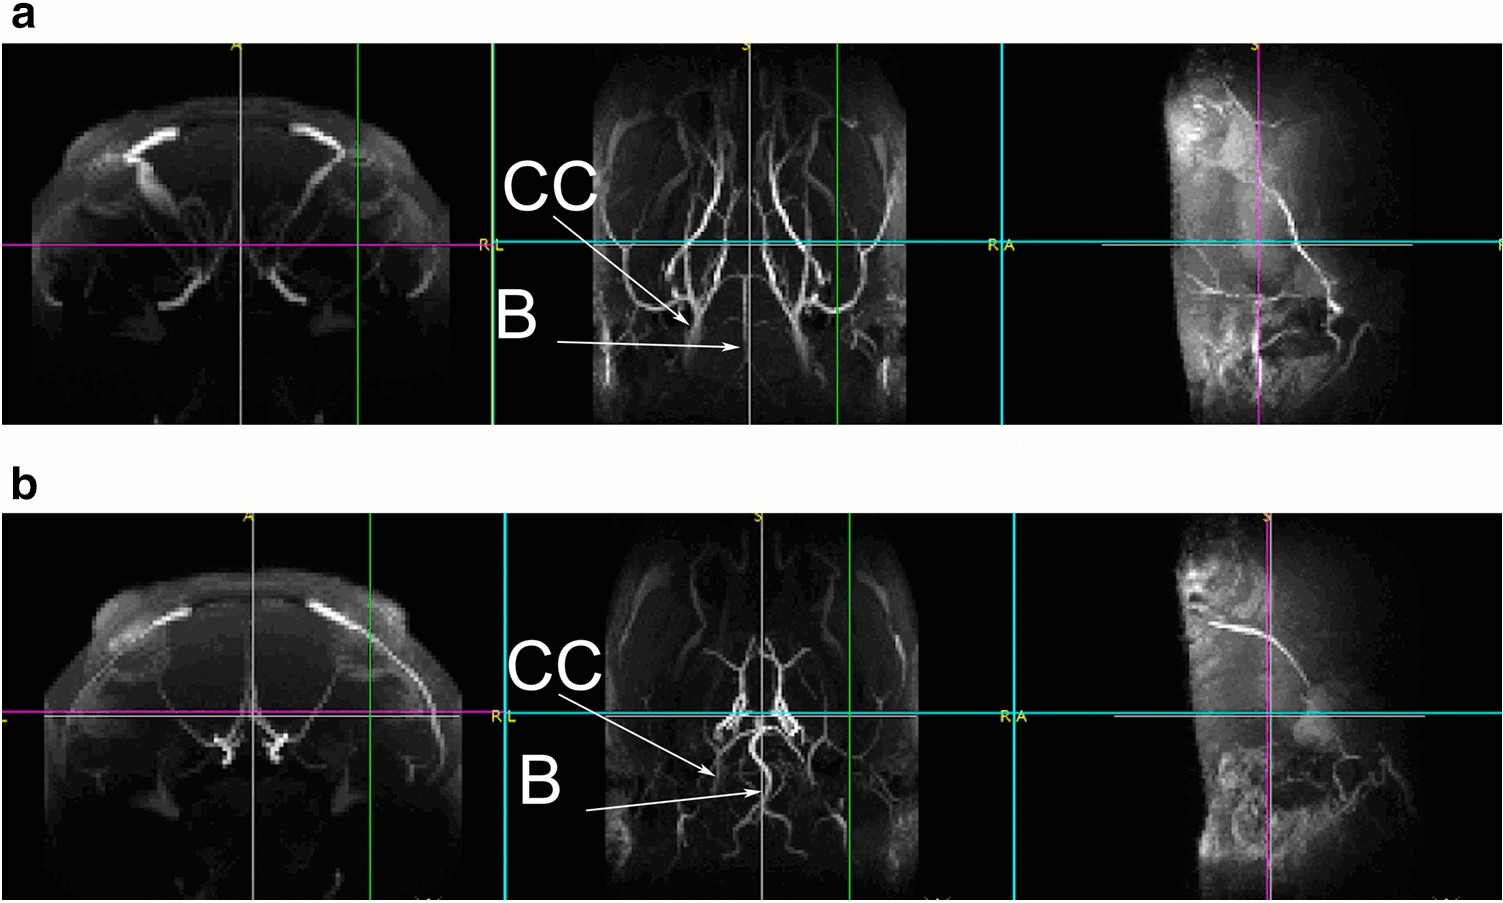

Figure 1

MRI validation of common carotid artery ligation 5 weeks after the occlusions. Representative image from horizontal view of a sham-operated rat (a) and an operated rat (b) (CC: arteria carotis communis; B: arteria basilaris). After the occlusion of common carotid arteries, the basilar artery was thickened (b).